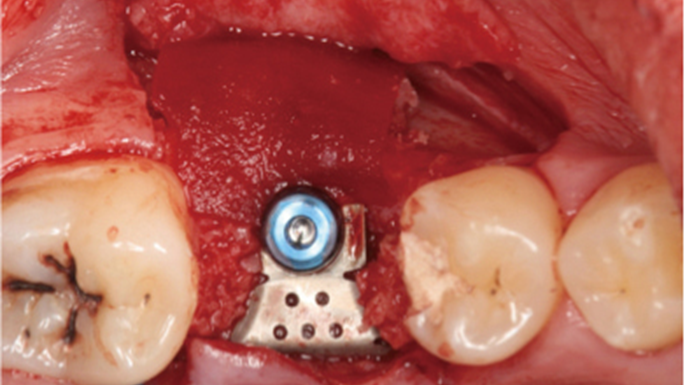

Clinical case: # 46 implant placement & GBR using i-Gen membrane for significant vertical resorption & mixed bone defect

- Courtesy of Dr. Iulian Filipov, Romania -

AnyRidge, mandibular posterior, i-Gen, resorption, bone defect, bone regeneration, space management, #46, GBR, Dr. Iulian Filipov

AnyRidge implant system, i-Gen